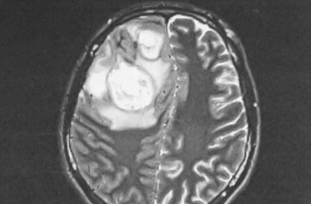

تصویر ۲: ام آر آی جمجمه در یک مرد ۵۸ ساله. آبسه با اندازه مشخص ۳۸×۲۸ میلی متر در لوب فرانتال چپ، جابجایی و فشرده سازی مشخصی در محفظه ی چپ ایجاد می کند. b MRIجمجمه در همان بیمار که پس از ۱۲ ماه به دلیل عود علائم بستری شده است. آبسه چند حفره ای نامنظم در لوب فرونتال چپ به ابعاد ۳۲×۲۴×۱۶ میلی متر

در ۲۵ بیمار، آبسه در سمت راست بود که شایع ترین عارضه ی یافت شده در تمام دورهها بود (۹ نفر در دوره ی اول، پنج مورد در دوره ی دوم و ۱۱ نفر در دوره ی سوم). تنها در یکی از بیماران مبتلا به آبسه ی لوب فرانتال چپ، آبسه های اپیدورال جمجمه و آمپیم ساب دورال وجود داشت. در بیمار دیگری، آبسه های فرانتال دو طرفه بودند. شانزده بیمار با آبسه ی اپیدورال (هفت، دو و هفت نفر به ترتیب در هر کدام از دوره های اول، دوم و آخر)، و نه بیمار با آمپیم ساب دورال (سه، یک و پنج نفر به ترتیب در هر کدام از دوره های اول، دوم و آخر) تشخیص داده شدند (شکل ۳).

در یکی از بیماران، چندین آبسه مغزی در لوب فرونتال و جداری مشاهده شد (شکل ۴). سه بیمار با ترومبوز سینوس علامت دار (۰، ۲ و ۱ در دوره های مربوطه) در کلینیک بستری شدند. دو بیمار سربریت داشتند. پانزده بیمار مبتلا به مننژیت بودند: هشت نفر با سبب شناسی استافیلوکوک یا استرپتوکوک و یک نفر هم با سبب شناسی ویروسی تشخیص داده شده. در دو بیمار، مایع مغزی نخاعی استریل بود (جدول ۲ و ۳).